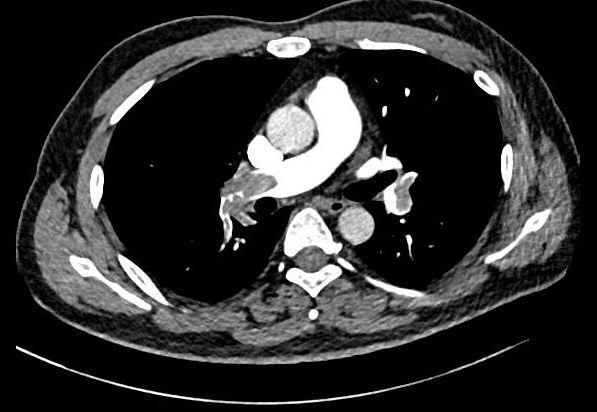

术前肺动脉CTA提示双肺动脉主干栓塞

生命体征:体温:37.6℃,脉搏:113次/分,呼吸:22次/分,血压:101/66mmHg(较平时收缩压降低20mmHg)。心脏超声:右心房室大,肺动脉收缩压约38mmHg,RV/LV约1.0。高危证据:肺栓塞严重指数(sPESI评分):2分,血流动力学不稳定、右心功能障碍、肌钙蛋白升高。